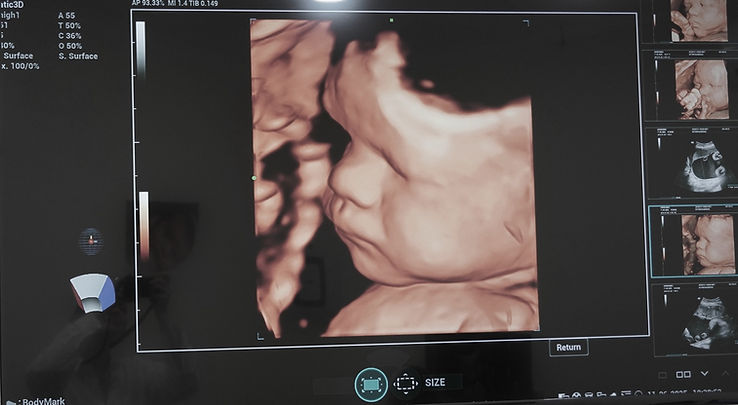

תובנות בזמן אמת על בריאותך. אולטרסאונד (USG) היא שיטת הדמיה לא פולשנית המשתמשת בגלי קול כדי לספק תמונות מפורטות של איברים פנימיים, רקמות וזרימת דם – ללא חשיפה לקרינה. זהו אחד מכלי האבחון המהימנים ביותר ברפואה המודרנית. מחלקת הרדיולוגיה שלנו מציעה הדמיה אבחנתית מתקדמת עם דגש חזק על גילוי מוקדם, דיוק קליני ונוחות המטופל. באמצעות ציוד אולטרסאונד חדיש ברזולוציה גבוהה, אנו מספקים בדיקות מפורטות של בלוטות התריס, איברי הבטן, השדיים, מבני האגן, אזורי השרירים והשלד ומערכות כלי הדם. שירותים אלה זמינים למבוגרים ולילדים כאחד, ותומכים באבחון מגוון רחב של מצבים, החל מחריגות באיברים ותהליכים דלקתיים ועד לבעיות מולדות ופגיעות ברקמות רכות. אולטרסאונד ילדים מבוצע בזהירות יתרה ובטכניקות מותאמות כדי להבטיח בטיחות, דיוק ולחץ מינימלי עבור המטופלים הצעירים ביותר שלנו. יכולות האולטרסאונד שלנו ממלאות תפקיד קריטי בגילוי מצבים כגון אבני מרה, מחלות כבד, שרירנים ברחם, ציסטות בשחלות ואנומליות בכלי הדם. סריקות גינקולוגיות וטרנס-ווגינליות מיוחדות תומכות עוד יותר בהערכות רבייה ואונקולוגיה בדיוק אבחוני גבוה. עבור הורים לעתיד, GI Rimon Med גאה להציע טכנולוגיית אולטרסאונד 4D, המספקת תמונות בזמן אמת של התינוק ברחם. סריקות מתקדמות אלו תומכות בבדיקות סקר טרום לידתיות באמצעות הערכות אנומליות עובריות מפורטות, הדמיית מבנה פנים וניטור תנועה. חוויית ה-4D משפרת הן את הדיוק הרפואי והן את הקשר הרגשי, ומציעה תובנות בלתי נשכחות במהלך ההריון. בין אם משמשים לטיפול ילדים, אבחון כללי או ניטור טרום לידתי, שירותי האולטרסאונד שלנו משקפים את מחויבות המרפאה לטיפול מקיף, ממוקד משפחה ומתקדם טכנולוגית